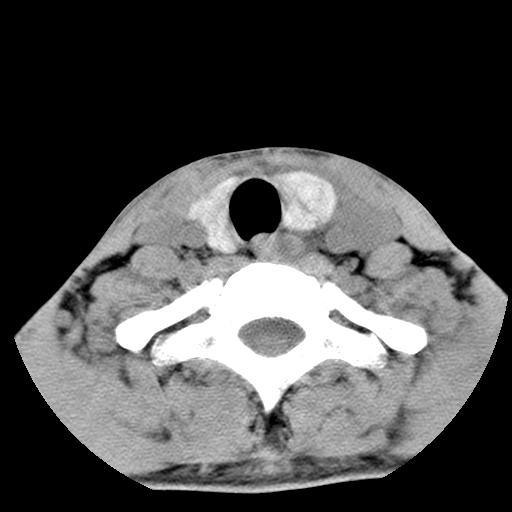

标题: CT15118:f-27y,左颈部肿一个月,无发热、无压痛 [打印本页]

标题: CT15118:f-27y,左颈部肿一个月,无发热、无压痛

1、甲状腺左叶病变:腺瘤?结节性增生?其他?

2、上极周围间隙病变。

3、2者关系?

左侧甲状腺肿大,密度不均.同侧甲状软骨似有破坏(建议传骨窗).左侧颈静脉增粗,各组织之间分界不清,有多个肿大淋巴结.甲状腺肿并感染?临床症状不符.淋巴结核?请结合其他检查.